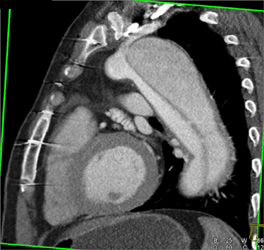

Diagnosis

Pulmonary Arteriovenous Malformation (PAVM)